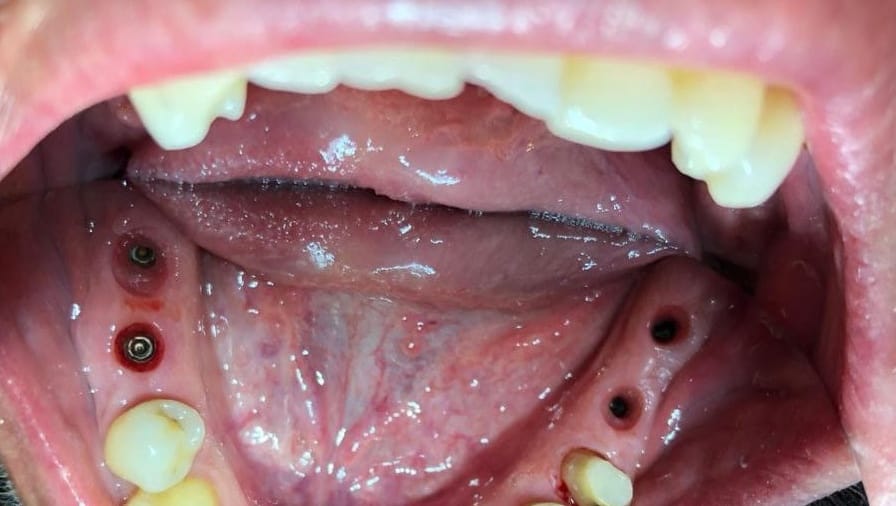

يتم إجراء عمليات الزرع في مراكزنا من قبل فريق من أخصائي زراعة الأسنان ذوي المهارات العالية وأطباء الأسنان التجميليين للحصول على دقة جراحية متميزة وجماليات ممتازة للابتسامة

يترأس مراكزنا فريق مختار بعناية من خبراء زراعة الأسنان. وبعد عملية الزرع يتم تركيب التيجان والجسور ، والتي يتم تصميمها بأقصى قدر من الدقة والجمالية لمنحك الابتسامة المثالية.

يتم تخطيط وتنفيذ إجراء زراعة الأسنان بعناية لضمان أن ترميم الأسنان يبدو طبيعيًا في الشكل واللون والمكان. نعطي الأولوية لراحة مرضانا بالإضافة إلى الجماليات. وهذا يتطلب مزيجًا مثاليًا من العبقرية الفنية والجراحية. لذلك ، يتم تنفيذ جميع حالات الزرع لدينا من قبل فريق من أطباء الأسنان التجميليين وأخصائي زراعة الأسنان.